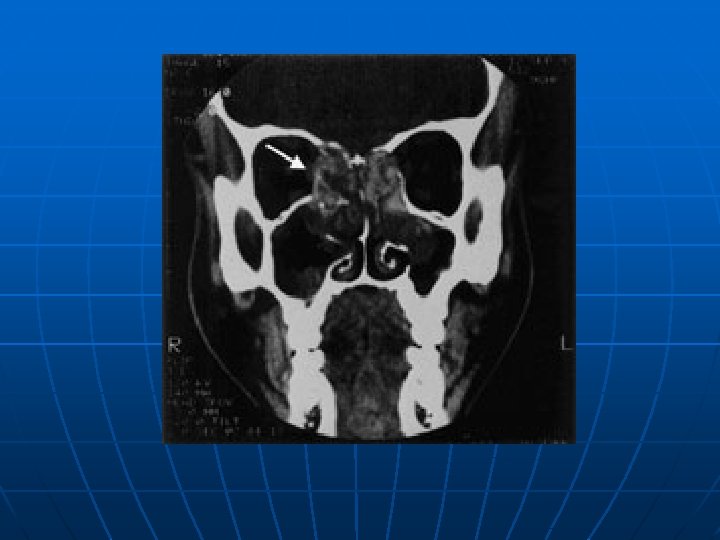

Viêm xoang n n Viêm mũi xoang là thông thường ở bệnh nhân nhiễm HIV, với báo cáo phổ biến từ 20 -68%. Lý do những bệnh nhân này quá dễ xảy ra nhiễm trùng là không hoàn toàn rõ ràng, nhưng thay đổi ở tế bào lông chuyển, cơ chế bảo vệ tại chổ cơ bản cho xoang, thì đã được báo cáo. [7] Bệnh nhân nhiễm HIV dường như có tỷ lệ cao hơn của S. aureus và P aerginosa nuôi cấy từ bệnh nhân với viêm xoang cấp và mạn tính, thường liên quan với vi khuẩn kỵ khí.

n n n P. aeruginosa , là mầm bệnh không thường gặp ở bệnh nhân miễn dịch tốt, chiếm khoảng lên tới 17% của viêm xoang cấp và 20% của viêm xoang mạn ở số dân nhiễm HIV. [5] Báo cáo đã mô tả viêm xoang do nấm với Alternaria alternata, Aspergillus, Pseudallescheria boydii, Cryptococcus, and Candida albicans. Báo cáo trường hợp đáng quan tâm khác mô tả viêm xoang gây nên bởi sinh vật đơn bào Acanthamoeba castellani